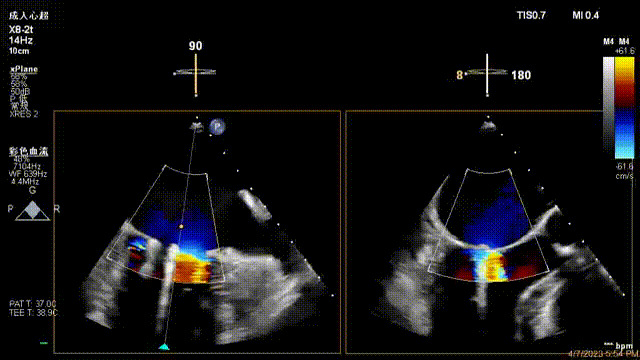

接受治療的是一例器質(zhì)性重度二尖瓣反流(DMR)患者,主訴“反復(fù)活動(dòng)后胸悶,氣促3年余”。術(shù)前超聲顯示,雙房增大,二尖瓣脫垂伴重度反流,輕度三尖瓣反流,輕度肺高壓,升主動(dòng)脈增寬。手術(shù)經(jīng)股靜脈-房間隔入路,采用全身麻醉插管,在TEE和DSA引導(dǎo)下完成房間隔穿刺。置入JensClip瓣膜夾系統(tǒng)后,在左房調(diào)整瓣膜夾的位置和軸向,后進(jìn)入左室,在TEE引導(dǎo)下捕捉二尖瓣前后瓣葉,并關(guān)閉瓣膜夾。經(jīng)TEE反復(fù)確認(rèn)手術(shù)效果后最終鎖定并釋放瓣膜夾。術(shù)后即刻超聲顯示瓣膜夾位置穩(wěn)定,功能良好,術(shù)前二尖瓣反流4+,術(shù)后0反流,肺靜脈逆流和左房壓都顯著好轉(zhuǎn),手術(shù)圓滿(mǎn)成功(以上數(shù)據(jù)都來(lái)源于醫(yī)院的臨床記錄)。術(shù)后患者狀態(tài)良好,目前已安排出院。

出院前隨訪(fǎng)超聲